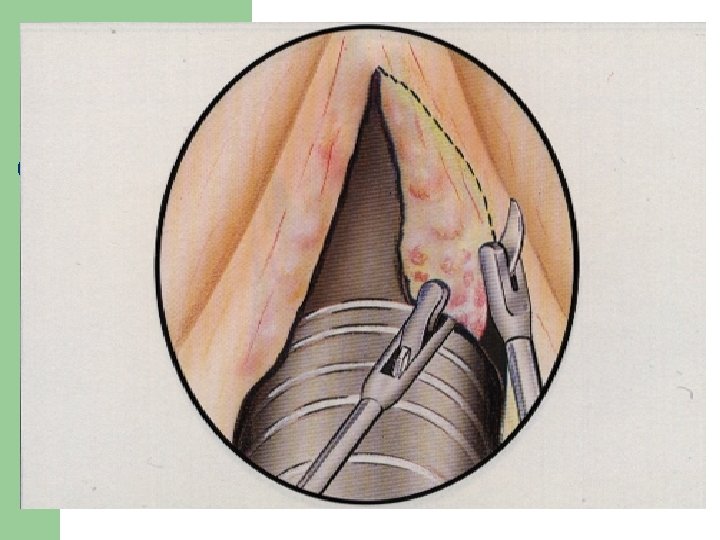

Vývoj dětské chraptivosti l 1. 2. 3. 4. Průvodním jevem při dětské chraptivosti je pokašlávání a pochrchlávání. Nález na hlasivkách postupuje takto: Hyperemické (překrvené hlasivky, Hypertrofické, vřetenovité zduření, hlasivkový uzávěr je neúplný a hlas má dyšnou příměs, ventrikulární řasy se začínají vyklenovat Zpěvácké uzlíčky, nejčastěji na hranicích přední a střední třetiny hlasivek Atrofie hlasivek až s podélnou rýhou, při fonaci nedomykavost uzávěru.

Hlasivkový uzlík l

Hlasivkový uzlík l

Hlasivkové uzlíky l